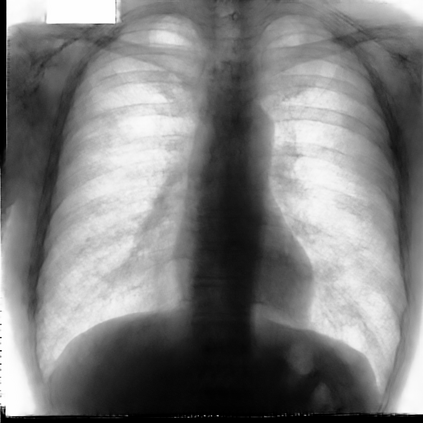

Multi-organ segmentation of X-ray images is of fundamental importance for computer aided diagnosis systems. However, the most advanced semantic segmentation methods rely on deep learning and require a huge amount of labeled images, which are rarely available due to both the high cost of human resources and the time required for labeling. In this paper, we present a novel multi-stage generation algorithm based on Generative Adversarial Networks (GANs) that can produce synthetic images along with their semantic labels and can be used for data augmentation. The main feature of the method is that, unlike other approaches, generation occurs in several stages, which simplifies the procedure and allows it to be used on very small datasets. The method has been evaluated on the segmentation of chest radiographic images, showing promising results. The multistage approach achieves state-of-the-art and, when very few images are used to train the GANs, outperforms the corresponding single-stage approach.